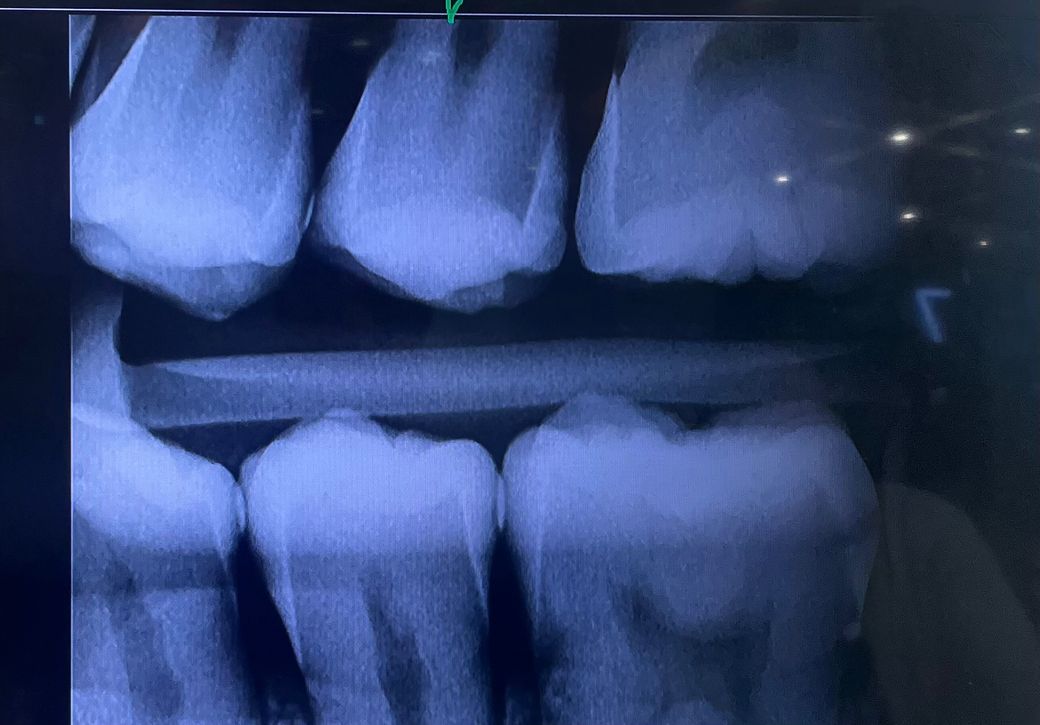

인접면 충치가 있는지 확인부탁드립니다!

해당 엑스레이 상으로 보았을 때 인접면 충치가 있는건가요? 있다면 어떤 치료 방법이 가장 나을까요? 또한 어느정도의 충치인지 알려주시면 감사하겠습니다.

왼쪽위의 제2소구치과 제1대구치 인접면에 충치가 있는 것으로 보입니다. 인접면충치의 경우 크라운이나 인레이 보철치료를 하게 됩니다.

충치의 범위가 넓어 충치를 제거하는도중에 신경이 노출된다면 신겨치료의 가능성이 있습니다.